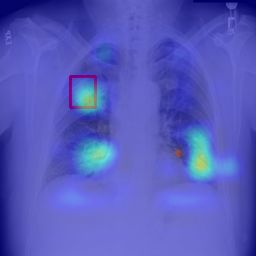

Deployments of artificial intelligence in medical diagnostics mandate not just accuracy and efficacy but also trust, emphasizing the need for explainability in machine decisions. The recent trend in automated medical image diagnostics leans towards the deployment of Transformer-based architectures, credited to their impressive capabilities. Since the self-attention feature of transformers contributes towards identifying crucial regions during the classification process, they enhance the trustability of the methods. However, the complex intricacies of these attention mechanisms may fall short of effectively pinpointing the regions of interest directly influencing AI decisions. Our research endeavors to innovate a unique attention block that underscores the correlation between 'regions' rather than 'pixels'. To address this challenge, we introduce an innovative system grounded in prototype learning, featuring an advanced self-attention mechanism that goes beyond conventional ad-hoc visual explanation techniques by offering comprehensible visual insights. A combined quantitative and qualitative methodological approach was used to demonstrate the effectiveness of the proposed method on the large-scale NIH chest X-ray dataset. Experimental results showed that our proposed method offers a promising direction for explainability, which can lead to the development of more trustable systems, which can facilitate easier and rapid adoption of such technology into routine clinics. The code is available at www.github.com/NUBagcilab/r2r_proto.